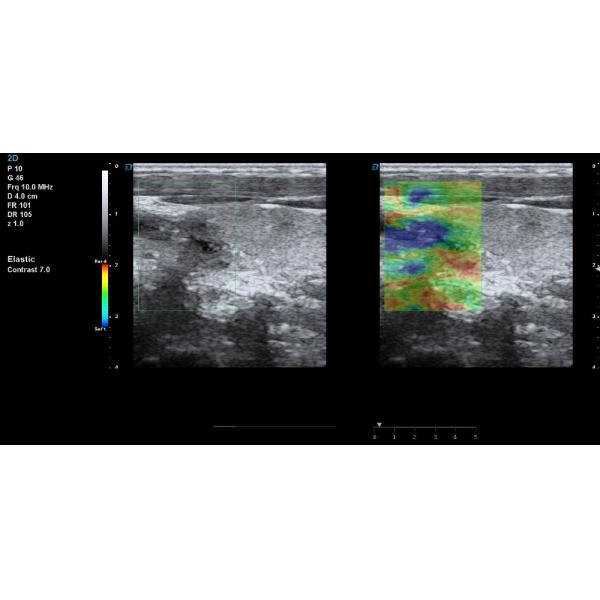

New arrival GH-T70 Elastography trolley ultrasonic scanner 4D cardiac color doppler ultrasound with TDI

4D Medical Ultrasound Machine Elastography Trolley Ultrasonic Scanning Machine Images |